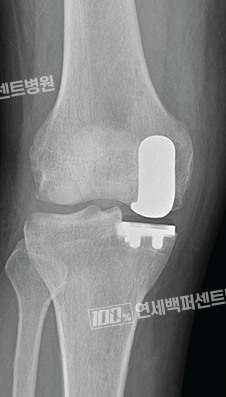

손상된 부분만 선택적으로,

부분 치환술(반치환술)

로봇으로 가능